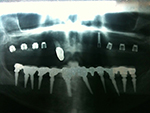

Die folgenden Patientenfälle sollen Ihnen einen Einblick in die Möglichkeiten der modernen Implantation geben.